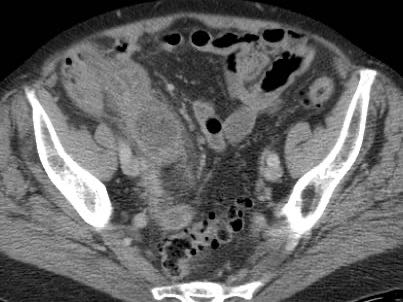

Dịch tự do

Một lượng nhỏ dịch trong phúc mạc giảm âm (*) có ít giá trị chẩn đoán và có thể gặp trong cả viêm ruột thừa cấp chưa thủng (trái) lẫn viêm ruột thừa thủng (mũi tên) (giữa), nhưng cũng có thể gặp ở bệnh nhân có ruột thừa bình thường (phải).

Lượng dịch lớn hơn, đặc biệt nếu khu trú và/hoặc đục, thường kèm theo liệt ruột khu trú hoặc toàn thể, là dấu hiệu nghi ngờ thủng.

Thông thường những bệnh nhân này có tình trạng nặng, đau nhiều và CRP tăng cao.

Ở người phụ nữ 56 tuổi này với CRP 180, siêu âm phát hiện dịch trong phúc mạc đục (*) và có thể thấy ruột thừa viêm với sỏi phân (mũi tên).

CT xác nhận hai sỏi phân ở hố chậu phải với hình ảnh khí bất thường, nghi ngờ viêm ruột thừa thủng.

Chọc hút dưới hướng dẫn siêu âm xác nhận dịch mủ.

Phẫu thuật cấp cứu phát hiện viêm ruột thừa thủng với nhiễm bẩn mủ bốn góc phần tư ổ bụng.